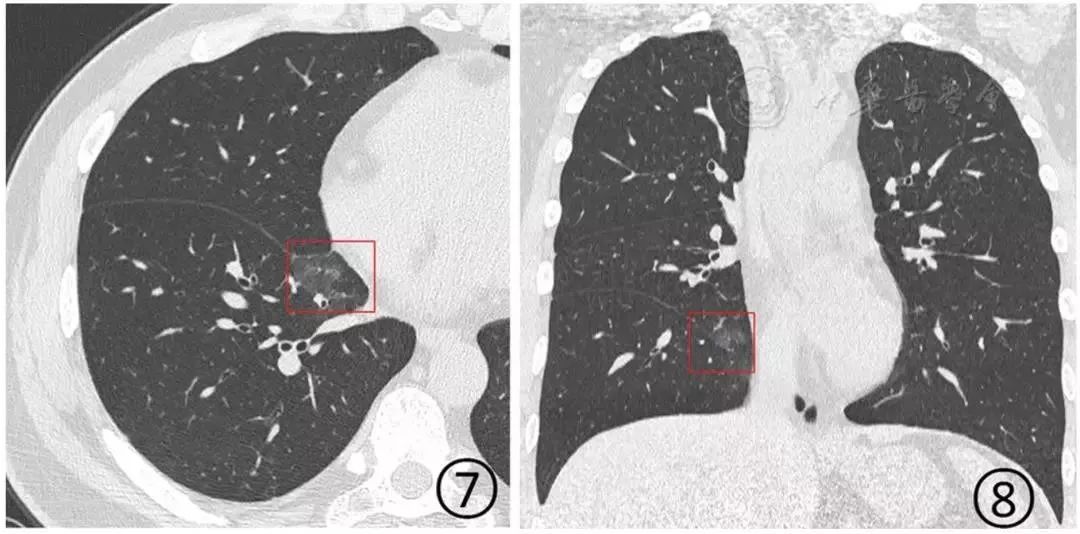

图7,8 :男,38岁。CT平扫横断面(图7)及冠状面(图8)显示右肺下叶内侧段非常淡薄的磨玻璃阴影(红色方框)

表现为单发或多发的局限性磨玻璃阴影、结节(图5,图6),非常淡薄的小斑片磨玻璃阴影(图7,图8)或者大片磨玻璃阴影(图9,图10),多数磨玻璃阴影边缘不清,部分边缘清晰。

病变多分布于中、下叶,多位于胸膜下(图5,图6)或叶间裂下(图7,图8),或者沿支气管血管束分布。